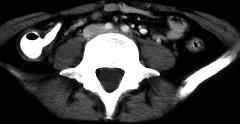

问题 女,32岁,腹痛、腹泻、便秘交替出现,粘液血便半年,里急后重,影像检查如图,最佳的诊断是 ( )

选项 A、溃疡性结肠炎 B、肠结核 C、慢性结肠炎 D、过敏性结肠炎 E、结肠癌

答案 A